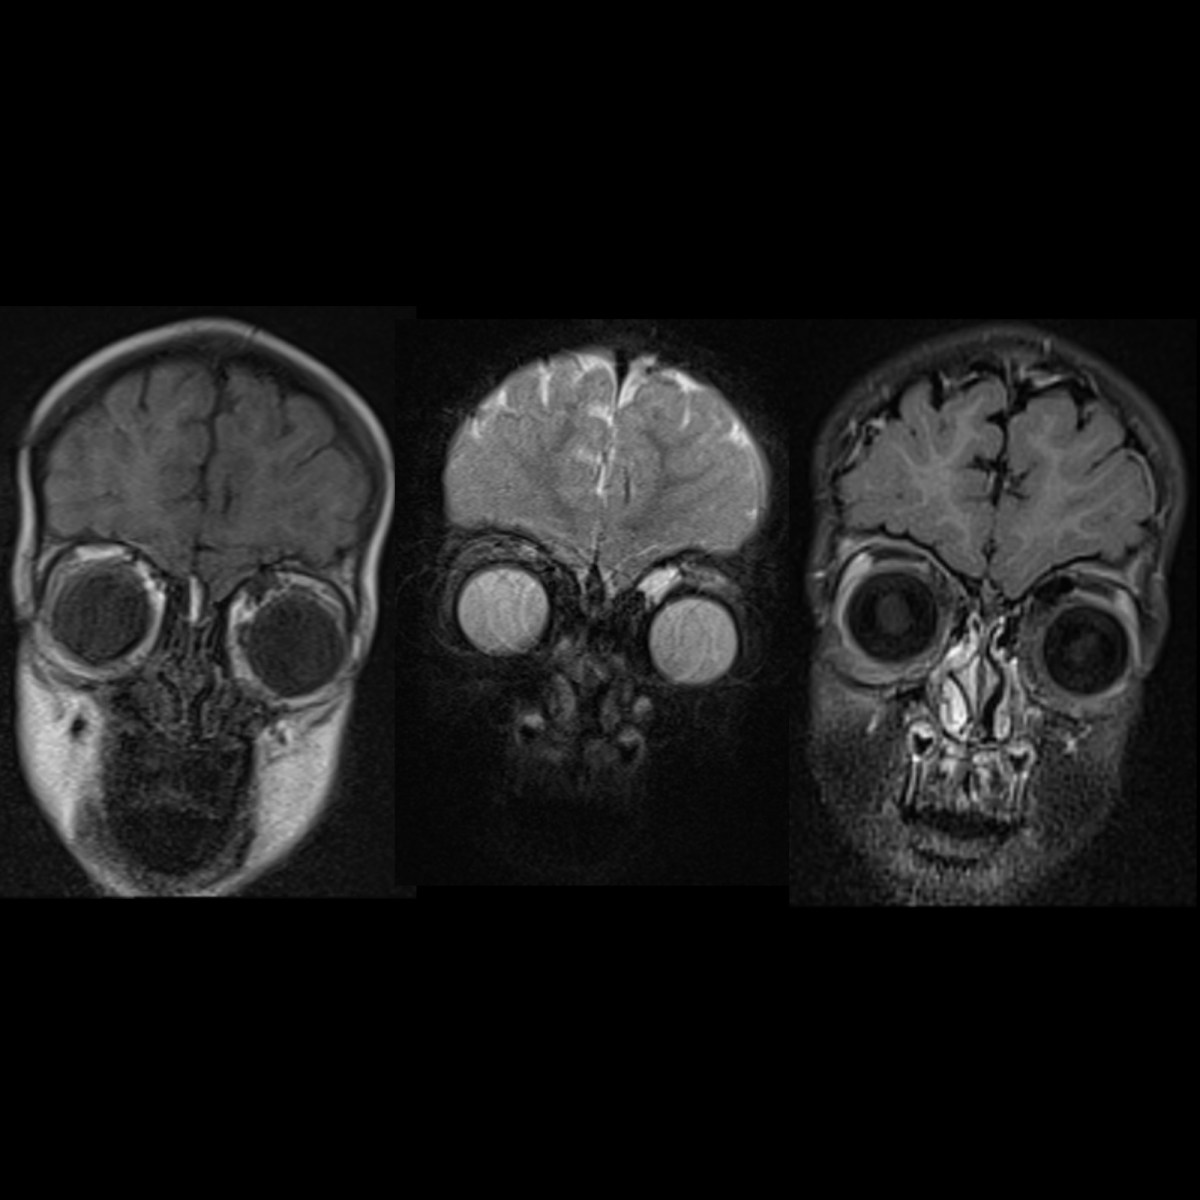

Facial Bones | Skull | Maxilla